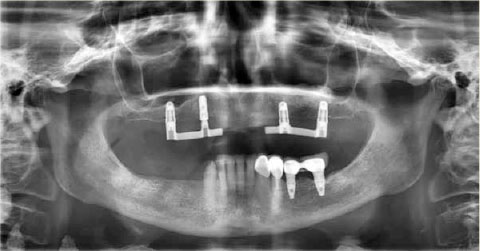

Een 77-jarige vrouwelijke patiënt meldt zich op verwijzing van een implantoloog bij de afdeling Radiologie voor een postoperatieve panoramaopname (afbeelding 1). Er zijn 4 implantaten geplaatst in de bovenkaak na een botaugmentatieprocedure in de sinus maxillaris links.

Afb. 1

Panoramaopname uit oktober 2017